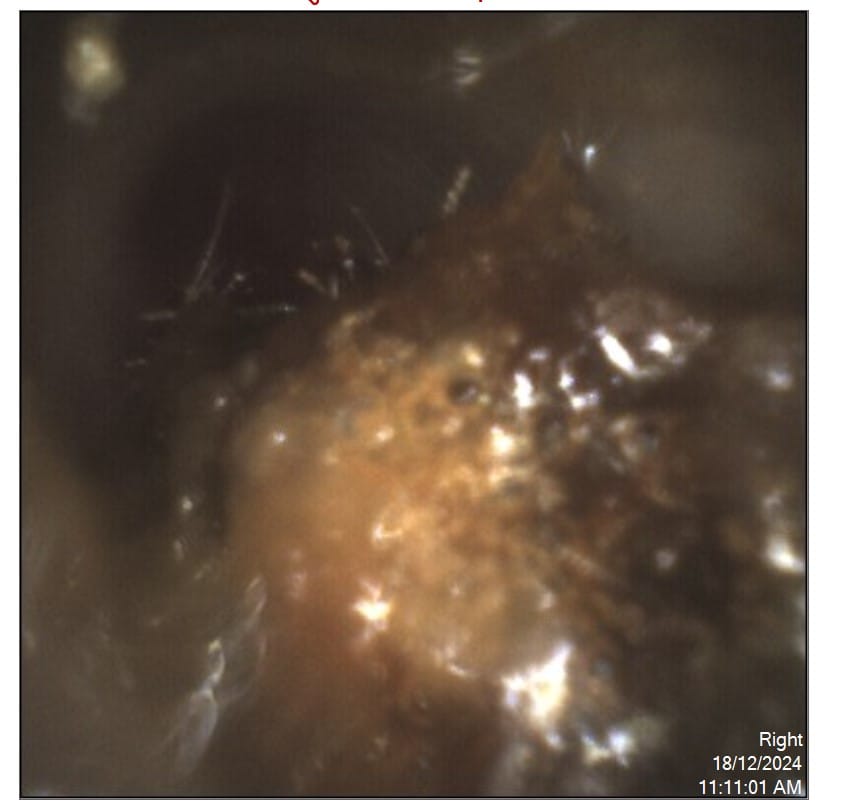

Have you ever felt like your ear is blocked, or that sounds seem muffled and distant? You might be experiencing impacted earwax, commonly known as “stuck […]

If you’ve ever experienced the frustration of blocked ears, you’ll know how uncomfortable it can be. Sounds become muffled, conversations feel harder to follow, and in […]

If you’ve ever had blocked ears, you know how frustrating it can be. Sounds become dull, voices are harder to follow, and sometimes you feel underwater. […]

Hearing health is integral to overall well-being, and earwax plays an important role in maintaining the health of your ears. Also known as cerumen, earwax protects […]